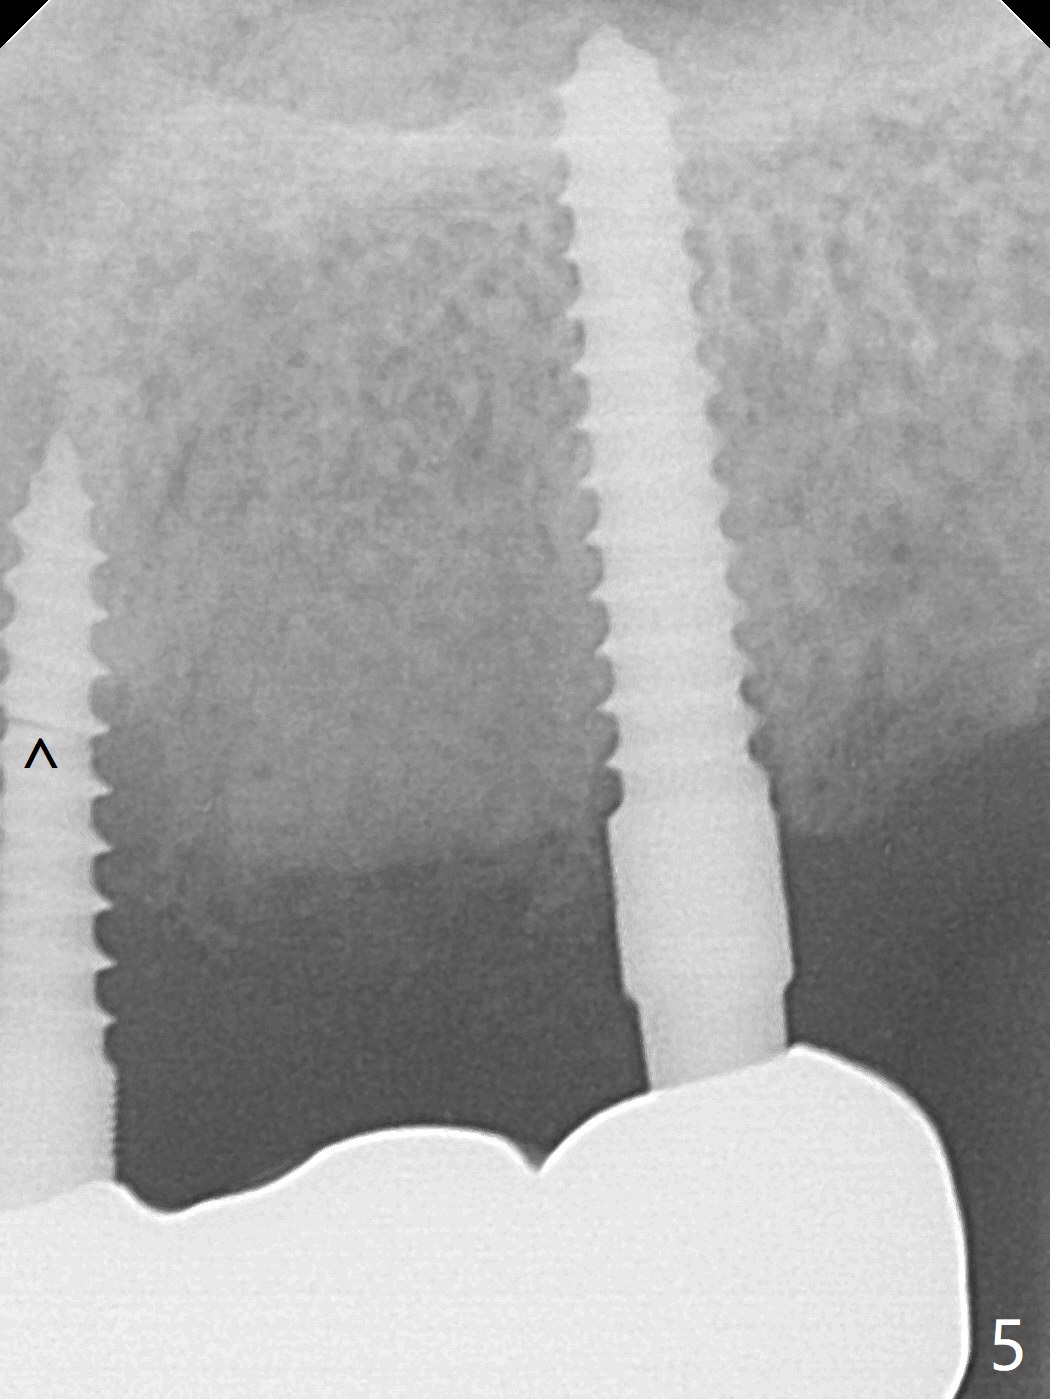

A 65-year-old woman will return to clinic with chief complaint of "loose top left implant bridge" 2.5 years post cementation. It appears that the implant at #9 is placed into the incisive canal (Fig.1 *) with coronal implant thread exposure (>). If it is true that the problem is #9. The denture tooth #8 will be removed so that the upper partial denture will be used a guide. One-piece implants will be placed at #8 and 10. The implant at #9 will be removed for bone graft as a future implant site, since the implant at #10 is 2 mm in diameter, vulnerable to fracture under mastication. If her vein is thin for PRF, consider using GEM21S to hydrate cortical bone. In fact the implant at #9 fractures at the junction of bone loss (Fig.4,5 ^). Full-mouth CT will be taken. Alginate impression will be taken for #8-10 surgical stent and provisional. Remove #8 denture tooth for implant placement with incision. Section the FPD between #10 and 11 for #10 implant placement using #9 broken implant as a guide when PA is taken. Remove the fractured implant and make a provisional.